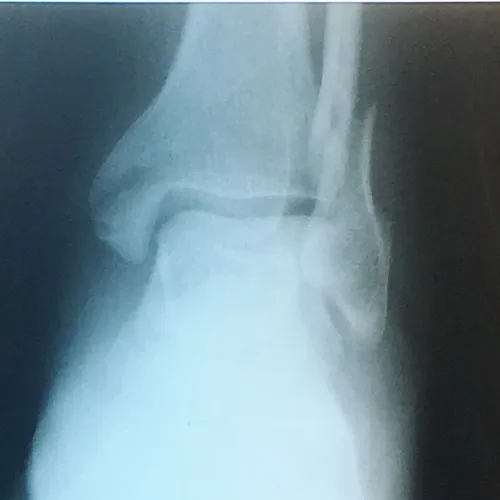

X-ray of Non Displaced Posterior Malleolar Fracture

CT scan sagittal views of minimal displaced posterior tibial malleolar fracture.